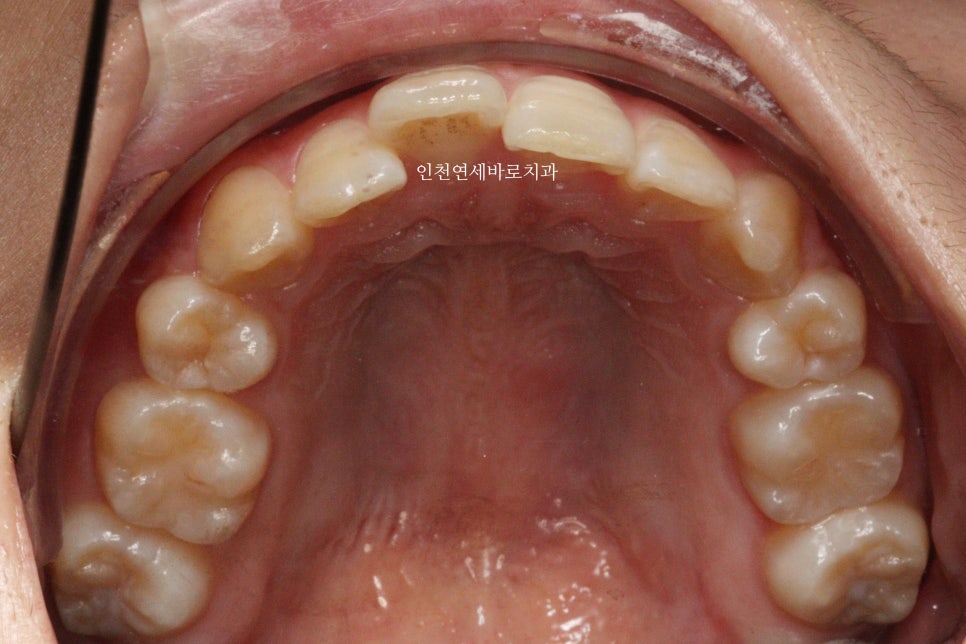

오늘은 교정이 끝난지 오래되어 재교정을 하고 싶어 내원했던 환자분 이야기 입니다.

예전에 중학생때 발치교정치료를 받았다고 합니다.

환자분의 나이는 이제 30대

약 15년만에 다시 교정치료를 결심하셨다고 합니다.

결혼을 앞둔 분이었고

앞니하나가 많이 틀어졌는데 점점 틀어진다고 하셨습니다.

철사 유지장치를 붙여놨었는데 오래전에 탈락 하고 다시 붙이지 않으셨다고 합니다.

변화모습입니다.